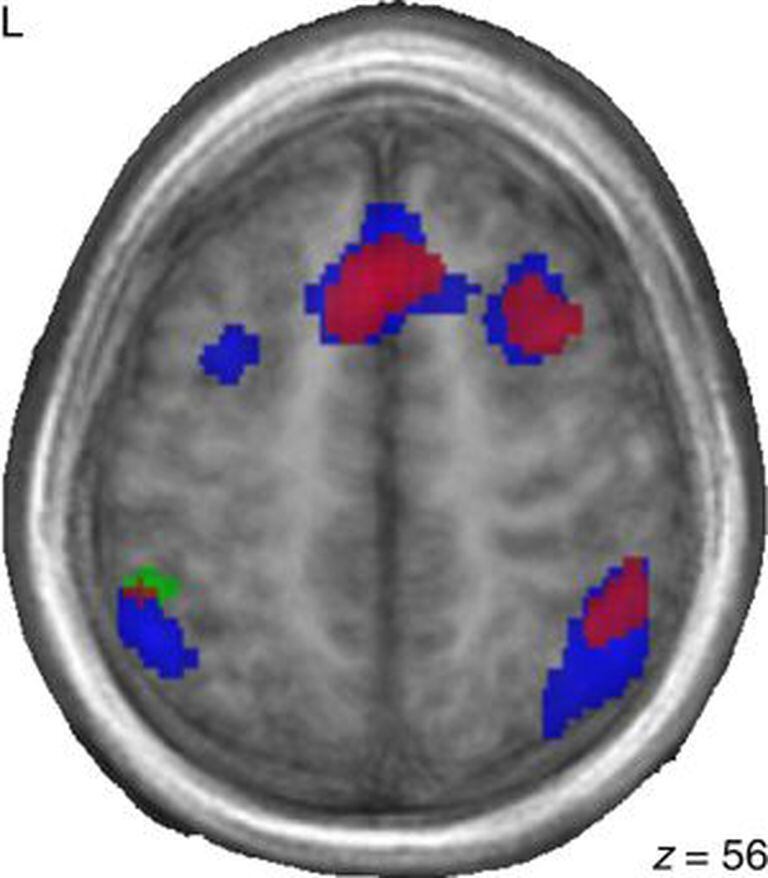

Durante a experiência, as crianças francesas e as estrangeiras adotadas ativaram as mesmas zonas cerebrais de processamento da linguagem. O segundo grupo, no entanto, usava áreas adicionais associadas às memórias de trabalho e auditiva e à atenção geral. "Esses resultados sugerem que as diferenças de aprendizagem que eles vivenciaram nos seus primeiros três anos de vida afetaram seus padrões cerebrais de ativação anos mais tarde”, diz Pierce.

As crianças chinesas que foram adotadas por famílias francesas utilizam mais as áreas cerebrais implicadas em tarefas de memória não verbal, e também as de atenção e processos de controle cognitivo, o que implica que as crianças adotadas apresentavam um processamento mais eficiente e competente no aprendizado de uma língua além do francês. Segundo os pesquisadores, isso demonstra a “extraordinária flexibilidade” do cérebro para se adaptar a novas circunstâncias ambientais e a utilização de sistemas alternativos para novos aprendizados se os sistemas iniciais não estiverem disponíveis.